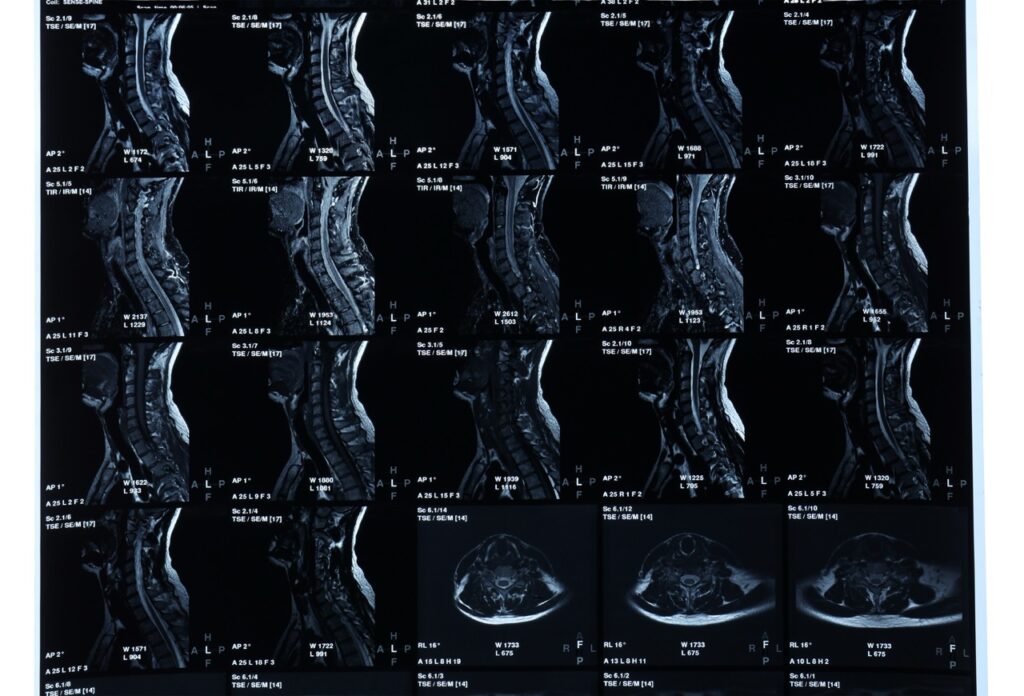

Understanding Your Cervical MRI Scan: What Every Patient Should Know Neck pain can be more than a daily discomfort, it can affect your movement, sleep, and overall quality of life. When symptoms like stiffness, tingling, or weakness spread into your shoulders or arms, your doctor may recommend a cervical MRI scan. This safe and advanced […]